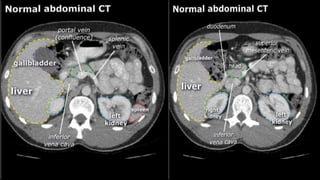

• A few characteristics of normal anatomy:

• Portal venous phase: the parenchyma of the

liver/spleen/pancreas is homogeneously enhanced.

• Intra-abdominal fat has the density of fat (HU -50 to -100;

see the X-ray/CT technique course for more information

about Hounsfield units); similar to normal subcutaneous fat.

If not, there may be ascites or fatty infiltration.

• A fewcharacteristics of normal anatomy: • Portal venous phase: the parenchyma of the liver/spleen/pancreas is homogeneously enhanced. • Intra-abdominal fat has the density of fat (HU -50 to -100; see the X-ray/CT technique course for more information about Hounsfield units); similar to normal subcutaneous fat. If not, there may be ascites or fatty infiltration.